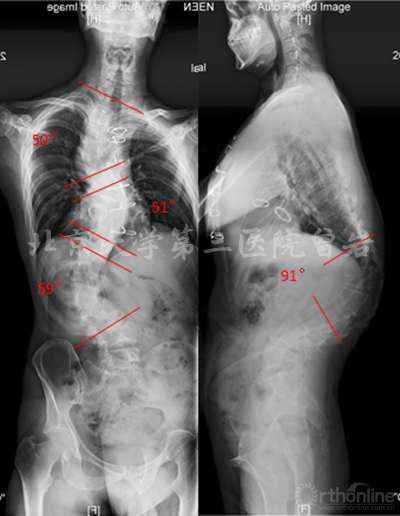

术前X线(图5):侧凸上胸弯Cobb 52°,下胸弯Cobb 52°,胸腰弯Cobb 65°,后凸角度102°,左肩高于右肩。

图5